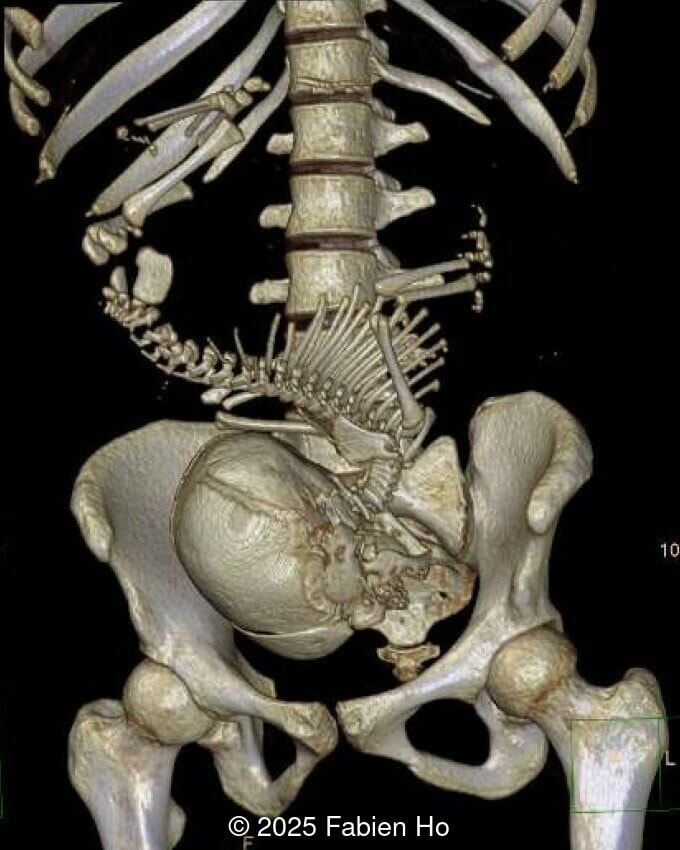

At 36 weeks gestation, the abdominal findings were unchanged however, the bones appeared short (<1st percentile) and the spine had an unusual appearance, therefore a computed tomography was performed at 37 weeks gestation.

- Short long bones (<1st percentile), normal mineralization, and no sign of lethal chondrodysplasia

- Dysostosis: Hemivertebrae L3, fused L4-L5, abnormal left foot with short metatarsals and missing phalanges

The couple chose to deliver naturally. After prenatal needle aspiration of the bladder, the baby was delivered at 39 weeks gestation. Postnatal findings were consistent with Prune-Belly Syndrome with flaccid abdominal wall (similar to prune skin), lower urinary tract obstruction in a male fetus, imperforate anus requiring colostomy, lumbar hemivertebrae, and left foot hypoplasia including metatarsals and phalanges.